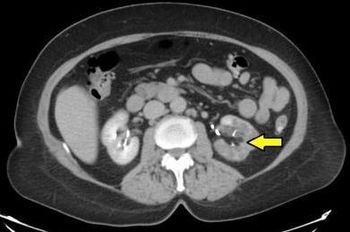

Acute renal infarction most often causes flank pain associated with nausea, vomiting, abdominal pain and, less frequently, fever.